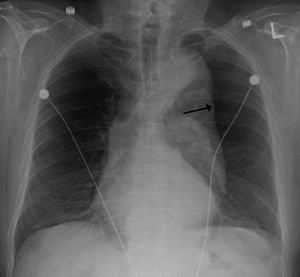

| Thoracic aortic aneurysm with arrow marking the lateral border of the aorta. | |

A thoracic aortic aneurysm is an aortic aneurysm that presents primarily in the thorax.

A thoracic aortic aneurysm is the "ballooning" of the upper aspect of the aorta, above the diaphragm. Untreated or unrecognized they can be fatal due to dissection or "popping" of the aneurysm leading to nearly instant death. Thoracic aneurysms are less common than an abdominal aortic aneurysm.[1] However, a syphilitic aneurysm is more likely to be a thoracic aortic aneurysm than an abdominal aortic aneurysm.